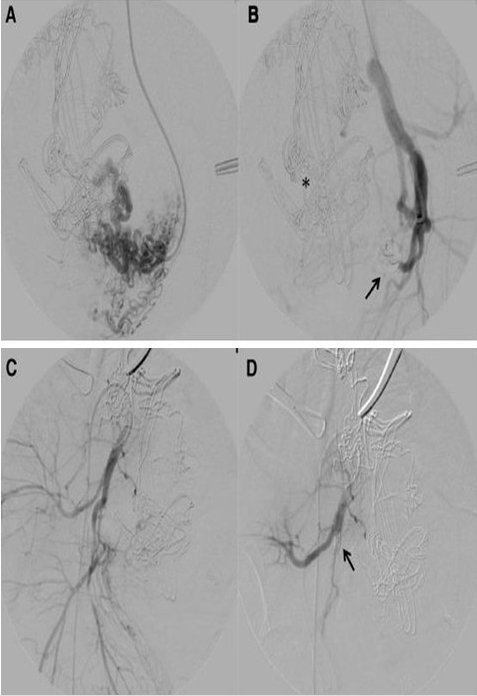

图 2:A. 选择性栓塞左侧子宫动脉;B. 超选择性导管线圈(箭头),血管造影显示子宫动脉已闭塞,注意腹腔内留置的止血纱布可阻碍血管造影可视化(星号);C. 右髂内动脉未见出血;D. 由于持续性出血,使用动脉可吸收明胶海绵线圈栓塞右侧子宫动脉(箭头)